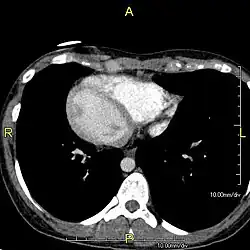

| Situs inversus causes the positions of the heart and lungs to be mirrored. | |

Situs inversus is found in about 0.01% of the population, or about 1 person in 10,000. In the most common situation, situs inversus totalis, it involves complete transposition (right to left reversal) of all of the viscera. The heart is not in its usual position in the left chest, but is on the right, a condition known as dextrocardia (lit. 'right-hearted'). Because the relationship between the organs is not changed, most people with situs inversus have no associated medical symptoms or complications.[1]

The condition affects all major structures within the thorax and abdomen. Generally, the organs are simply transposed through the sagittal plane. The heart is located on the right side of the thorax, the stomach and spleen on the right side of the abdomen and the liver and gall bladder on the left side. The heart's normal right atrium occurs on the left, and the left atrium is on the right. The lung anatomy is reversed and the left lung has three lobes while the right lung has two lobes. The intestines and other internal structures are also reversed from the normal, and the blood vessels, nerves, and lymphatics are also transposed.

If the heart is swapped to the right side of the thorax, it is known as "situs inversus with dextrocardia" or "situs inversus totalis". If the heart remains on the normal left side of the thorax, a much rarer condition (1 in 2,000,000 of the general population), it is known as "situs inversus with levocardia" or "situs inversus incompletus".

Diagnosis of situs inversus can be made using imaging techniques such as x-ray, ultrasound, CT scan, and magnetic resonance imaging (MRI).[9]